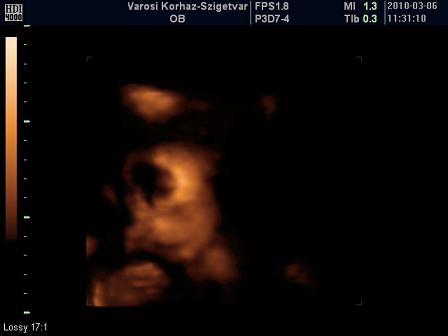

Köszönjük a Nóci dicséreteket!!!:) Találtam egy képecskét a cd-n, ahol még egy picit az arcocskája is látszik:) Sajna nem lettek túl jök a képek :( De ebbe a képbe teljesen beleszerelmesedtem! :) A Nóciba már réééég fülig vagyok esve :)

Íme a kis pofija: (csak kár hogy "lyukas a feje" )